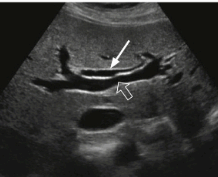

- 간내담관(intrahepatic bile duct)의 좌우직경은 2mm 이하이다. 직경이 2mm 이상이거나 portal vein 직경의 40% 이상일 때는 확장된 걸로 간주한다.

intrahepatic duct measurement (left)

intrahepatic duct measurement(right)